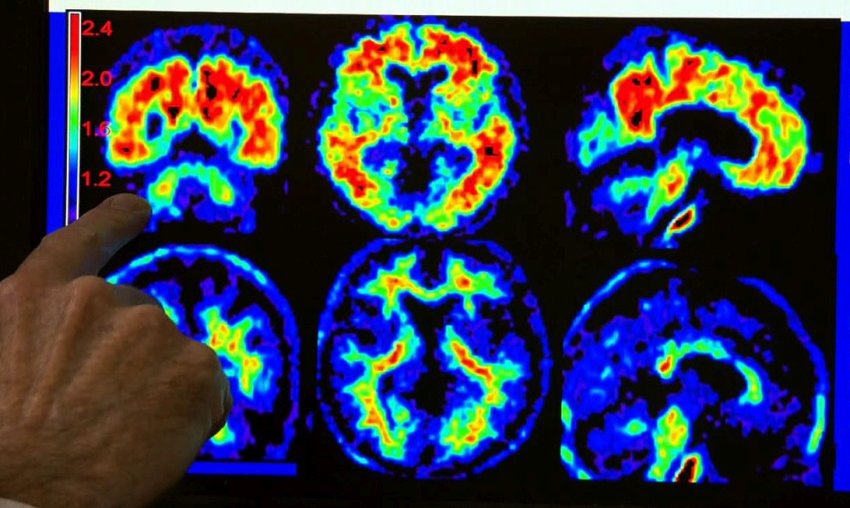

I farmaci antiipertensivi differiscono riguardo al rallentamento del declino cognitivo correlato all'età? Questo è oggetto di un ampio dibattito [rif. 1,2,3,4,5,6].I 'bloccanti del recettore II dell'angiotensina' (ARB, angiotensin receptor II blockers)...